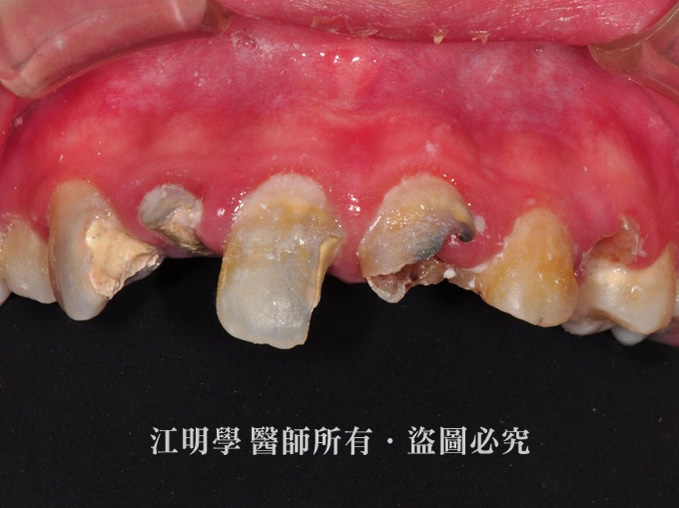

多顆牙齒嚴重蛀牙

治療前:蛀牙、牙齦發炎狀況嚴重。

治療後:蛀牙已完全改善,牙齦恢復健康